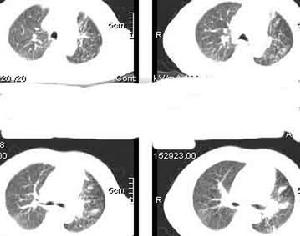

肺炎治療方案

小兒支原體肺炎的治療與一般肺炎的治療原則基本相同,採取綜合治療措施。包括一般治療、對症治療、抗生素的套用、腎上腺皮質激素,以及肺外併發症的治療等5個方面 。目前抗生素的治療尚屬主要治療方法,青黴素類,頭孢類抗生素的普遍套用,大大緩解了患者的痛苦,縮短了治療周期,抗生素對各種由細菌引起疾病均有較好的療法,針對有肺炎桿菌引起的肺炎,呼吸道感染,青黴素類如:青黴素V鉀,青黴素G。頭孢類抗生素,如頭孢氨苄、頭孢拉丁。此類藥物作為有細菌引起的呼吸系統疾病有較好的治療效果。一般治療

肺炎胸片呼吸道隔離由於支原體感染可造成小流行,且患兒病後排支原體的時間較長,可達1~2個月之外。嬰兒時期僅表現為上呼吸道感染症狀,在重複感染後才發生肺炎。同時在感染支原體期間容易再感染其它病毒,導致病情加重遷延不愈。因此,對患兒或有密切接觸史的小兒,應儘可能做到呼吸道隔離,以防止再感染和交叉感染。

肺炎患者胸片靜脈注射紅黴素乳糖酸鹽300mg,4min的血濃度平均為40.9μg/ml,2h後為2.6μg/ml,6h後為0.32μg/ml。如每12h連續靜脈滴注紅黴素乳糖酸鹽1g,則8h後的血藥濃度可維持4~6μg/ml。而痰中平均嘗試為2.6(0.9~8.4)μg/ml。紅黴素主要經膽汁排泄,部分可從腸道內重新吸收。相當量的紅黴素在肝內代謝滅活。